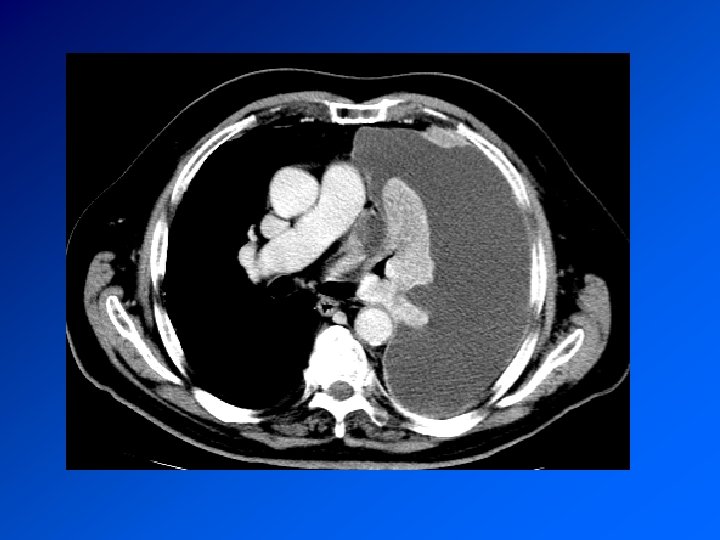

Enquête diagnostique Histoire de la maladie : recherche une maladie déjà connue, une exposition à un toxique professionnel, la prise de médicaments Examen clinique retrouve le syndrome pleural. Recherche de signes d’autres maladies associée Radio de thorax : fait le diagnostic TDM Thorax : précise les images Ponction pleurale oriente en fonction de la cytologie

Mésothéliome pleural Cancer primitif de la plèvre Principal facteur de risque (retrouvé dans > 80% des méso): exposition à l’AMIANTE CDD : AEG douleur, syndrome pleural. Surveillance d’un sujet exposé Radio : pleurésie. Epaississement tumoral nodulaire de la plèvre. Extension extrathoracique rare mais possible Evolution défavorable. Survie moyenne 9 à 12 mois. Traitement décevant : chimiothérapie. Radiothérapie sur orifices biopsies et drainage Symphise pleurale